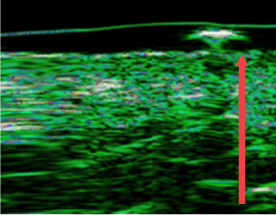

04. 皮肤真皮层厚度变化

可对因老化、频繁手术、外部刺激而变薄的皮肤真皮层进行改善

• radiesse_img11

施术前

• radiesse_img12

四个月后

(真皮层厚度增加12%)

• radiesse_img13

7个月后

(真皮层厚度增加27%)